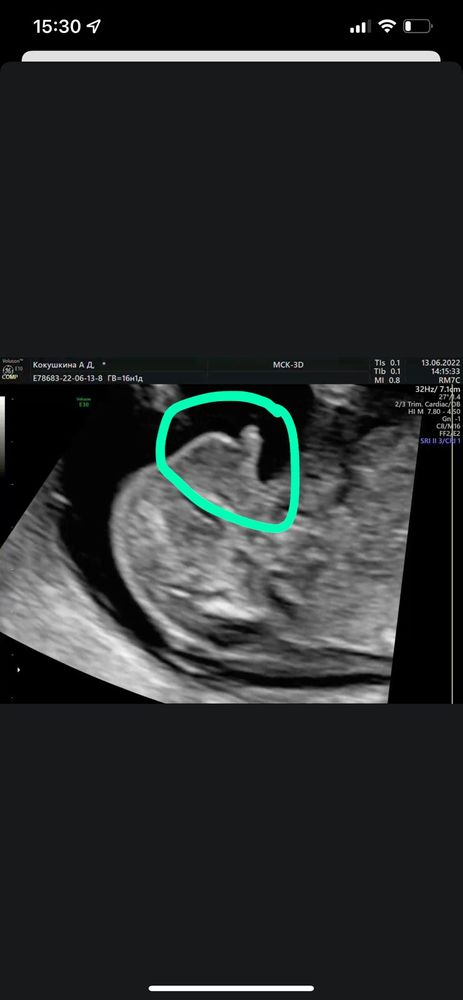

Всем привет!) предположил врач мальчика, я читала что можно по наклону пипирки понять мальчик или девочка) кто-нибудь умеет определять?) это точно не ноги, скриншот с видео, это именно то что между ног🤣 мне все таки кажется или там прям пипирка пацанская?😅